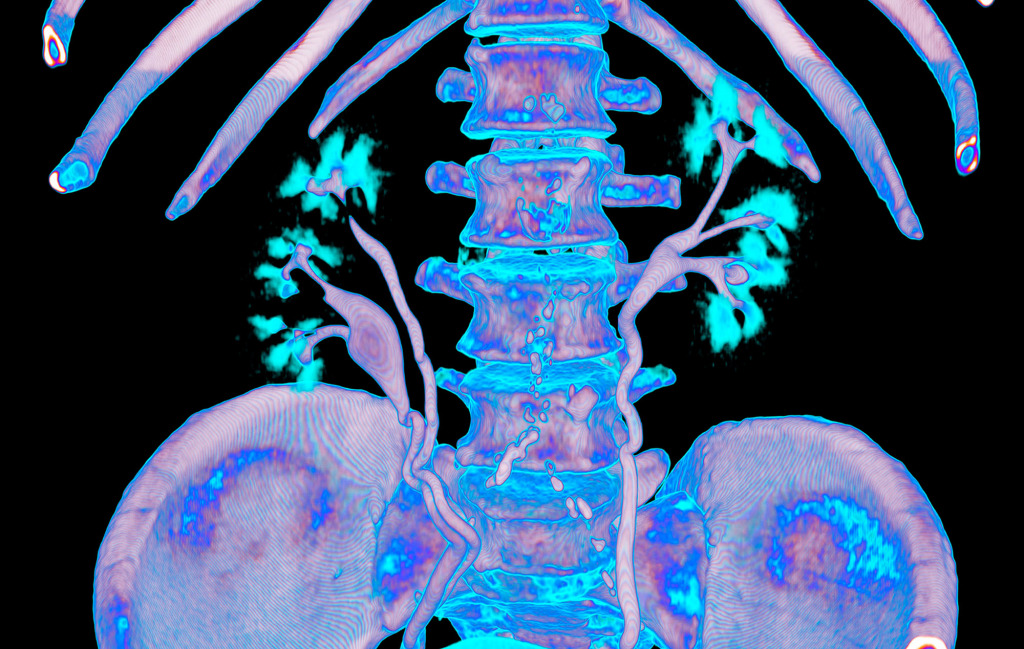

The program for processing radiological images (DICOM archives) allows you to create and look at a three-dimensional image from different angles.

If you change the location of the virtual lens, thereby changing the perspective, you can get such images.

I simply create a table where the radiological density of the material can correspond to any colour.

After combining different shades, I only have to choose what I like the most.

No. Tissues with different densities are best suited to visualisation by CT imaging.

Lungs and heart, bones and muscles or organs injected with a contrast agent reveal the best structure and anatomy.